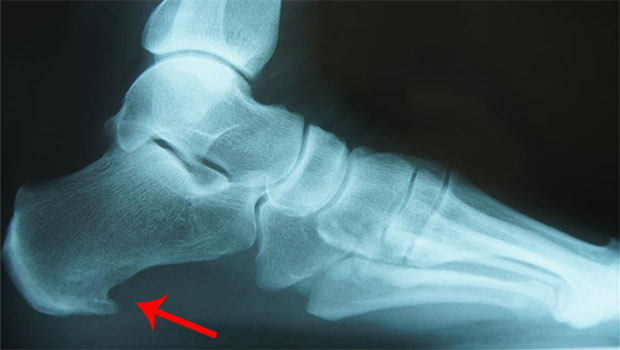

El espolón calcáneo es la calcificación de la unión de la fascia plantar con el hueso calcáneo (talón) y generalmente ocurre por una fascitis plantar crónica que no ha sido tratada. En la Rx se aprecia como una calcificación en forma de espina de rosa o espuela, de ahí su nombre.

La fascitis plantar no requiere exámenes complejos, ya que el exámen físico y la historia clínica pueden identificar el problema: sensibilidad localizada, ubicar la zona de dolor y palpar nódulos y zonas inflamadas. En pocas ocasiones se solicita ecografía o resonancia magnética cuando el diagnóstico es confuso o coexiste con otra patología que debamos realizar diagnóstico diferencial. Se puede identificar el espolón calcáneo en la Rx y en dichos exámenes.